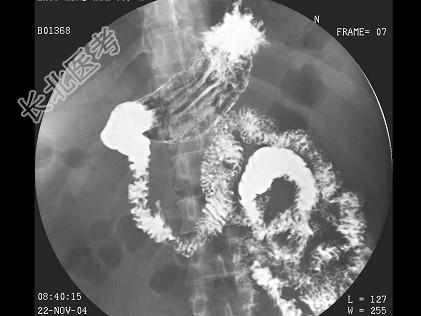

- 单项选择题男,35岁, 左侧腹痛半年,阵发性。结合图像, 最可能的诊断为 ( )

A、正常肠圈

B、十二指肠炎

C、球部溃疡

D、降段憩室

E、水平段憩室